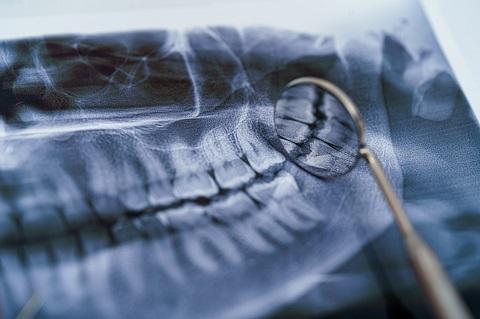

Oferujemy wysokiej jakości badania diagnostyczne, takie jak: RTG punktowe, pantomogram, cefalometria, tomografia CBCT, cyfrowy skan zębów oraz dentystyczny protokół fotograficzny.

Efektywne leczenie stomatologiczne w większości przypadków wymaga dokładnej diagnostyki, opierającej się na zobrazowaniu stanu uzębienia, kości szczęki czy żuchwy. Jednym z popularnych sposobów diagnostyki stomatologicznej jest zdjęcie pantomograficzne, czyli pantomogram. Pozwala ono uzyskać precyzyjny obraz struktur, z odwzorowaniem wszelkich krzywizn i ewentualnych nieprawidłowości. Zaawansowaną diagnostykę zapewnia tomografia komputerowa CBCT, która oferuje obrazowanie w technologii 3D.